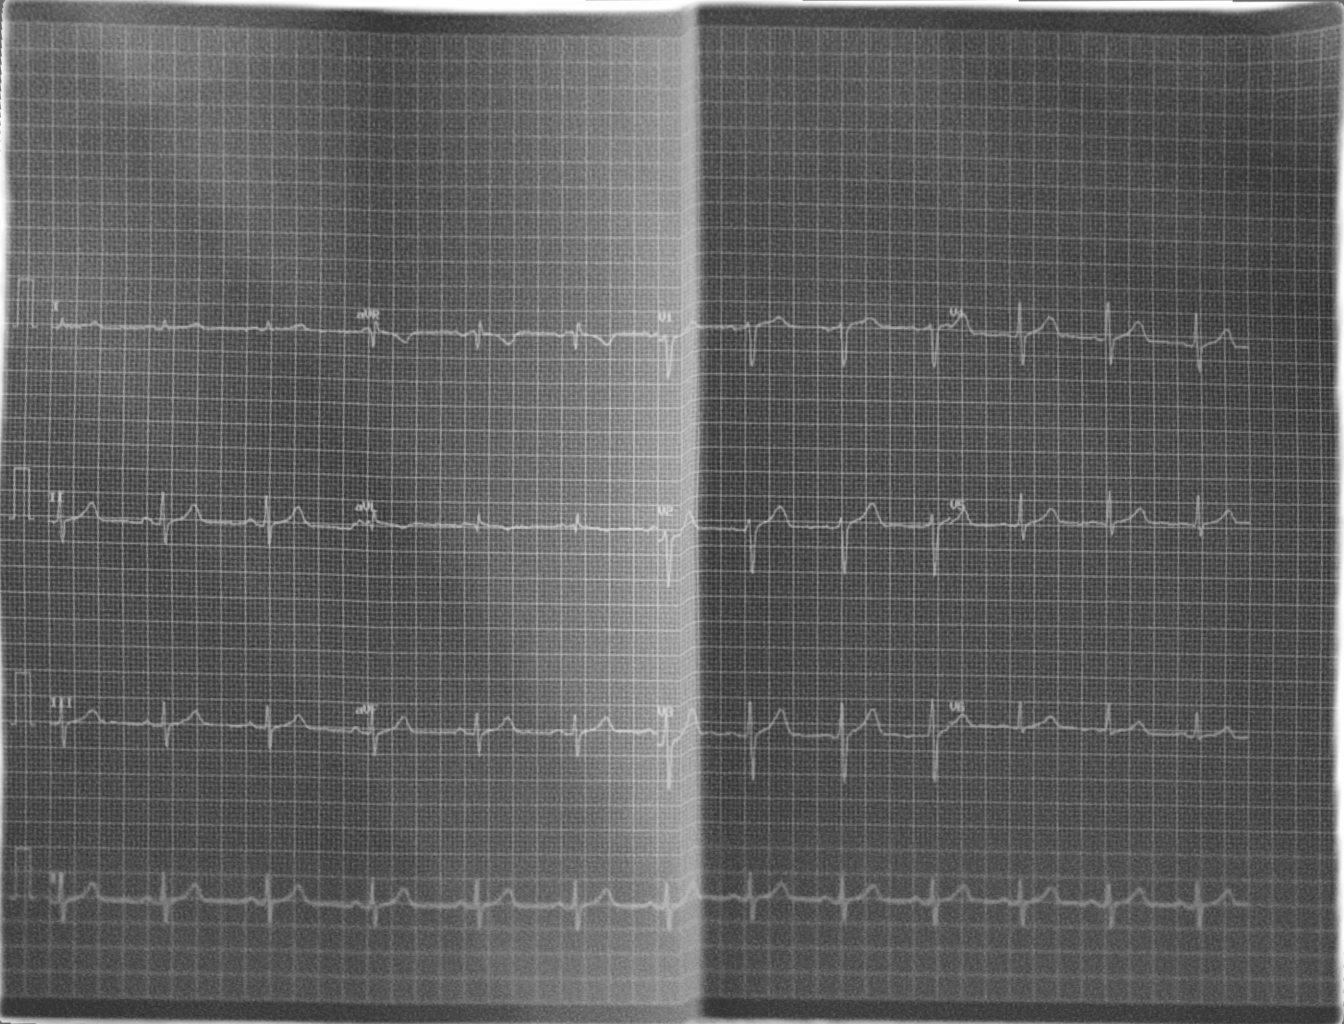

The ECG images used in this study were synthetically generated from the GenECG dataset, where lighting conditions often introduced contrast artifacts. To address this, we applied Contrast Limited Adaptive Histogram Equalization (CLAHE) [8], a technique to effectively normalize the image contrast. Subsequently, we utilized the segmentation-based tool Rembg [9] to remove the background from the images, isolating the ECG paper. An example of an image from the GenECG dataset is shown in Fig. 2.

With the successful training of the new model, the segmentation step was eliminated, thereby simplifying the process. An example grayscale ECG image, obtained by transforming the image in Fig. 2, is shown in Fig. 7.